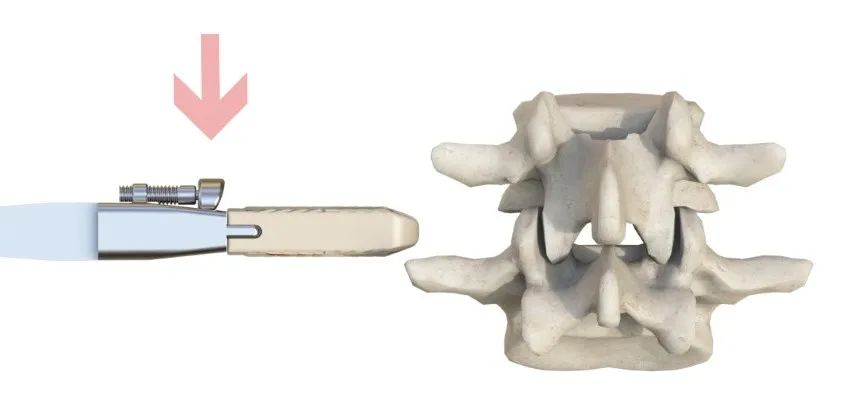

預彎的固定夾設計,交叉式自導(dao)向打入

安全簡單的操作方式(shi)

限深可調,融合器植入位置(zhi)更精準(zhun)

融合器工具(ju)展示